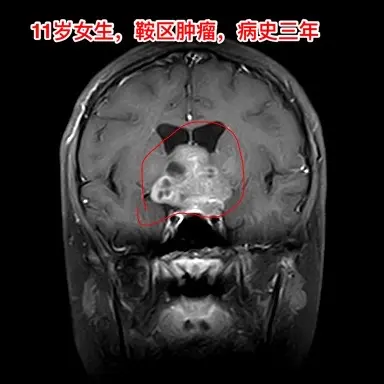

生殖细胞瘤对化疗很敏感,降低颅压才安全。之前我发的11岁四川女孩子,因多饮多尿、视力下降、多睡等症状在我科住院。住院后经用药物治疗,精神状态明显好转。 我们怀疑肿瘤为生殖细胞瘤,因肿瘤体积巨大,综合考虑病史、体检、手术风险、对化疗、放疗的敏感性,我们于8月13日给患儿作了肿瘤活检手术。 手术后病理报告为纯生殖细胞瘤,未见其他肿瘤成分(当然活检取得的标本很少,这个结论不是百分百的可靠) 8月20日开始化疗,8月21日患儿出现精神差、多睡症状,和住院前的症状相似。复查CT显示肿瘤在活检手术后继续增大,而且造成了脑积水,颅压高,见图2。此时不得不为患儿作急诊脑室外引流手术,以求降低颅压,为化疗保驾护航。随后继续化疗。 化疗的第三天,CT显示肿瘤体积有所缩小,见图4。 化疗一周后,肿瘤体积显著变小了,脑积水明显减轻了,见图5。病人的精神状态好转。拔除了脑室引流管。 希望化疗能将肿瘤完全杀灭,再结合放疗,将肿瘤完全治愈。